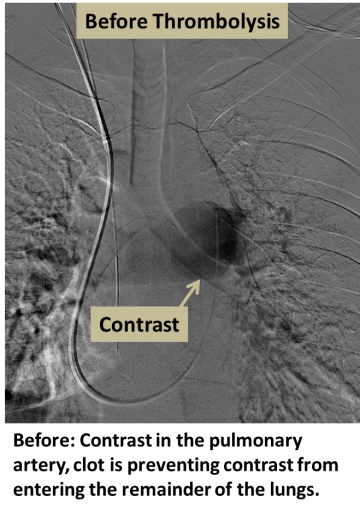

Before: Contrast in the pulmonary artery, clot is preventing contrast from entering the remainder of the lungs